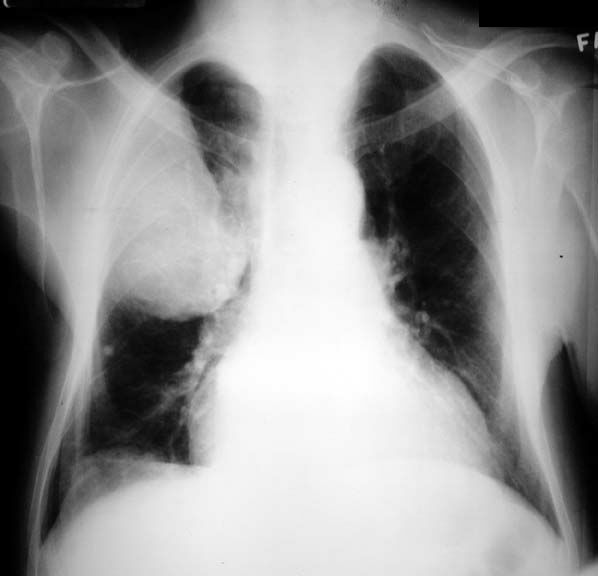

Extrapleural Lesion

• Mass density

• Pleural based

• Sharp inner margin, indistinct outer margin

• Expanding rib lesion

Once the lesion becomes this large, the angle of contact with the chest wall is not concave and the cat under the rug appearance is no longer present.

Colon ca with rib metastases.